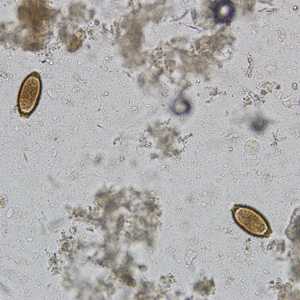

February - 2008 - Case #221

A survey was conducted to determine the prevalence of geohelminth infections in school-age children living in Haiti. The laboratory aspect of the survey consisted of processing stool specimens which were collected in 10% formalin.